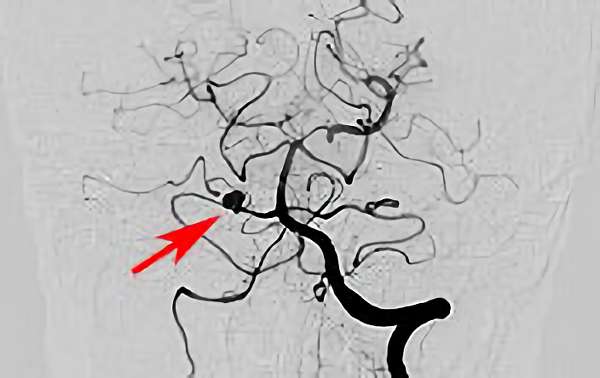

No.1631 手術前